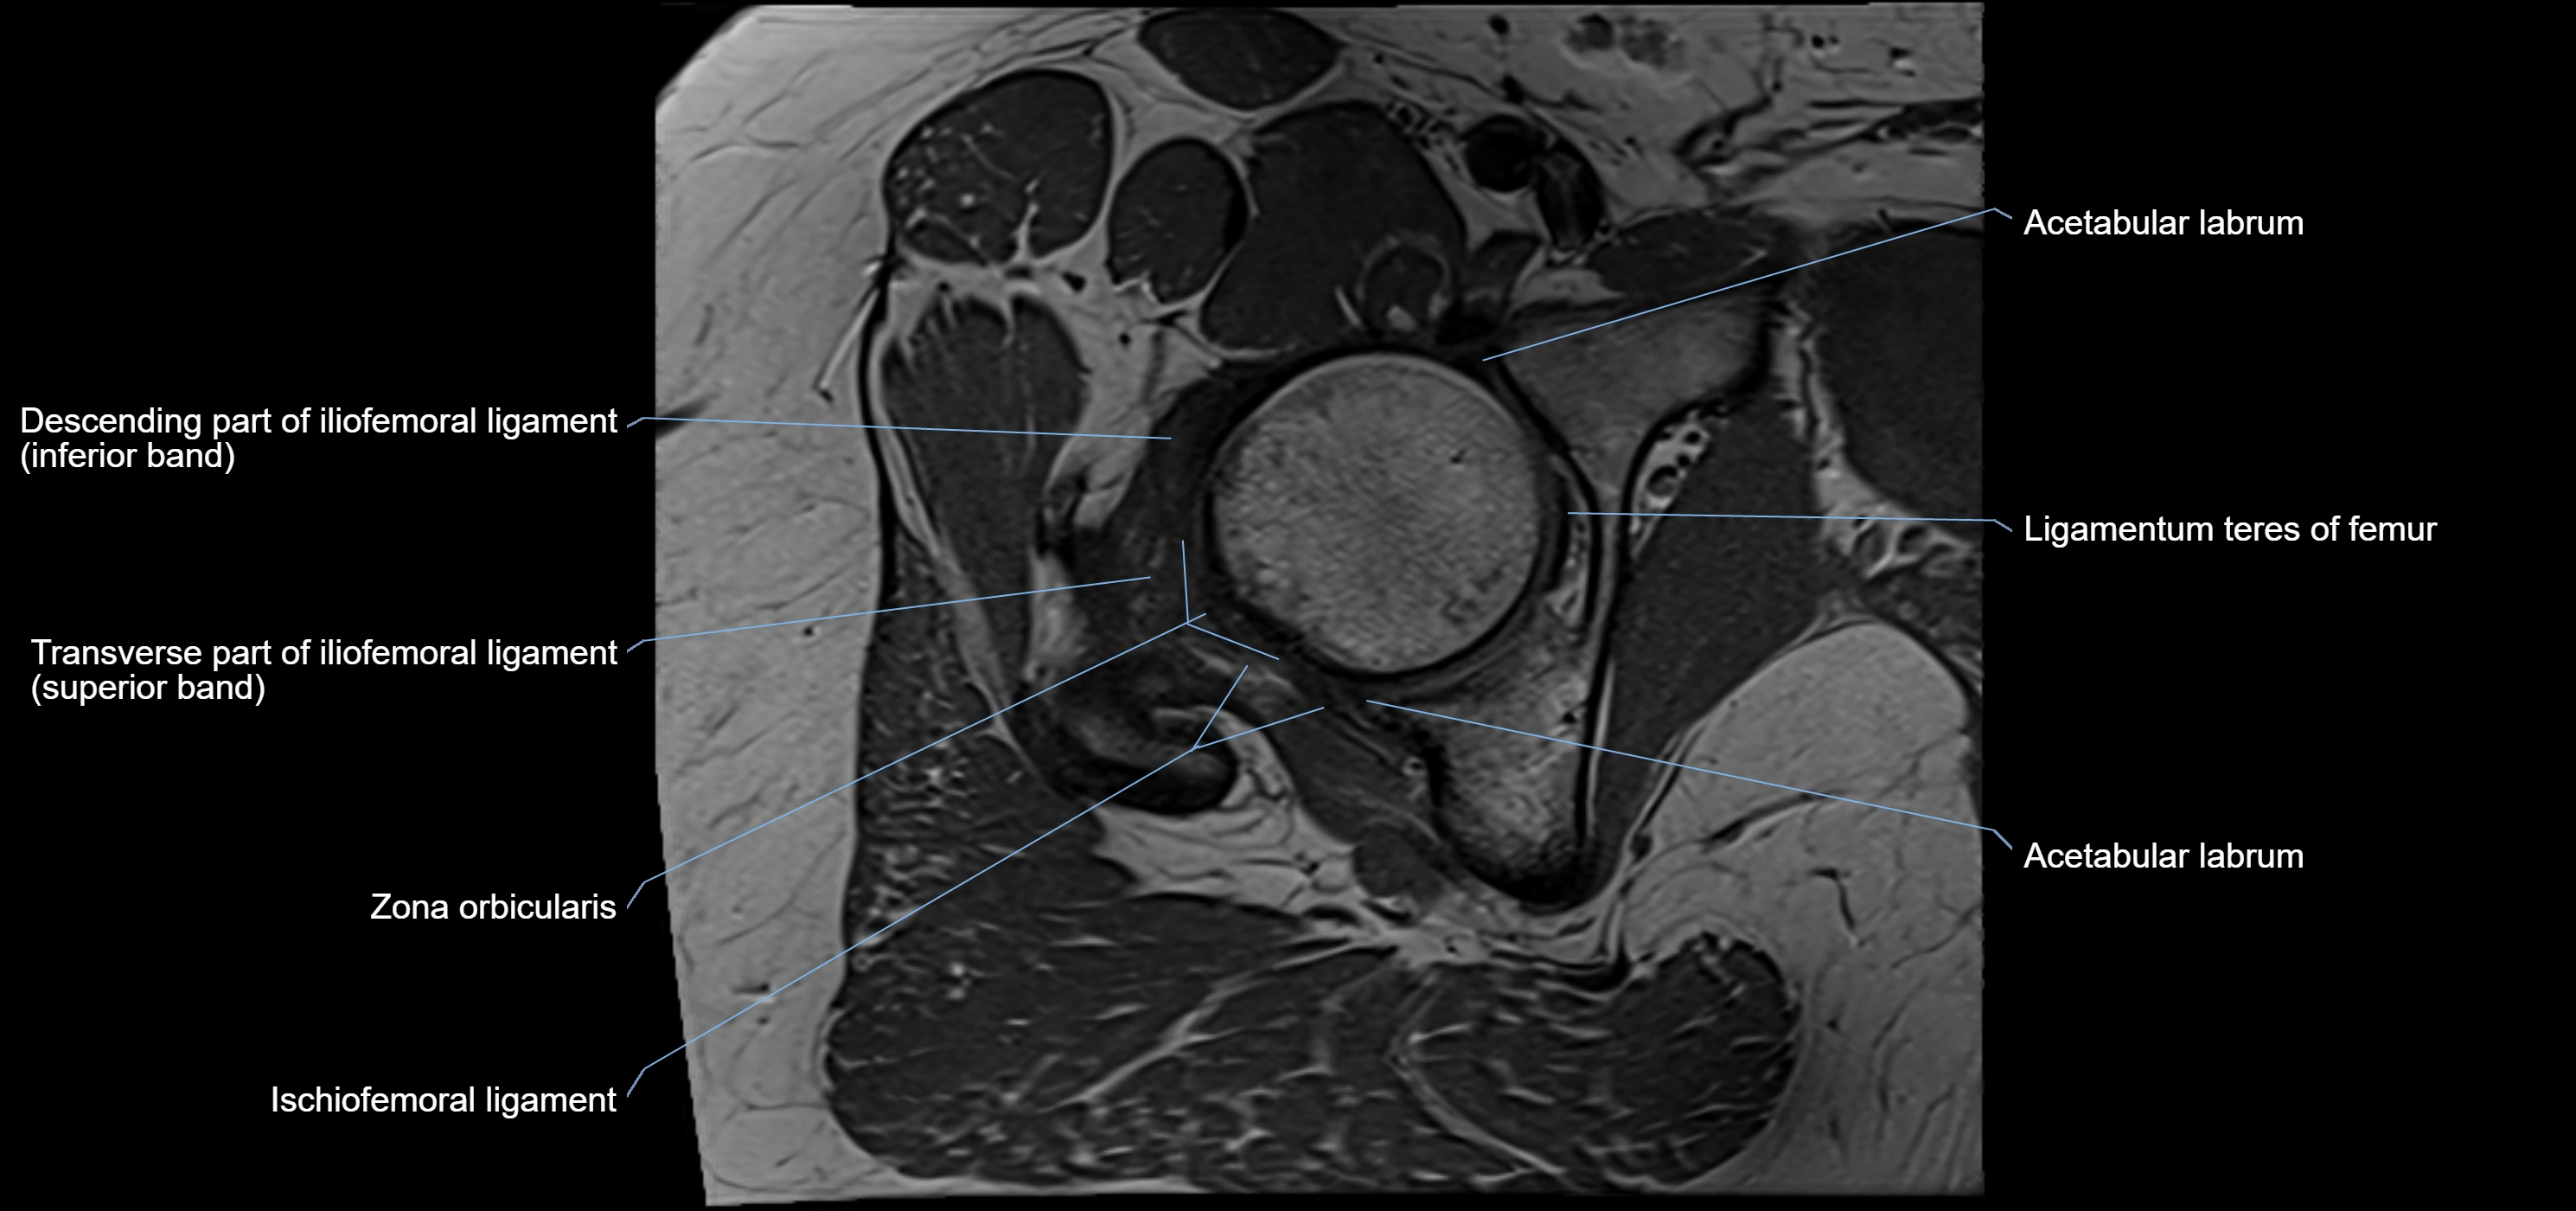

MRI Appearance

T1-weighted images:

• Labrum: low signal intensity (dark)

• Surrounded by intermediate signal joint fluid (bright on arthrogram)

• Tears: linear or focal areas of intermediate-to-high signal interrupting labral continuity

T2-weighted images:

• Joint fluid: bright, making labral tears visible as fluid extending into or around labrum

• Degeneration: may show areas of increased signal within labrum

MRI image

image